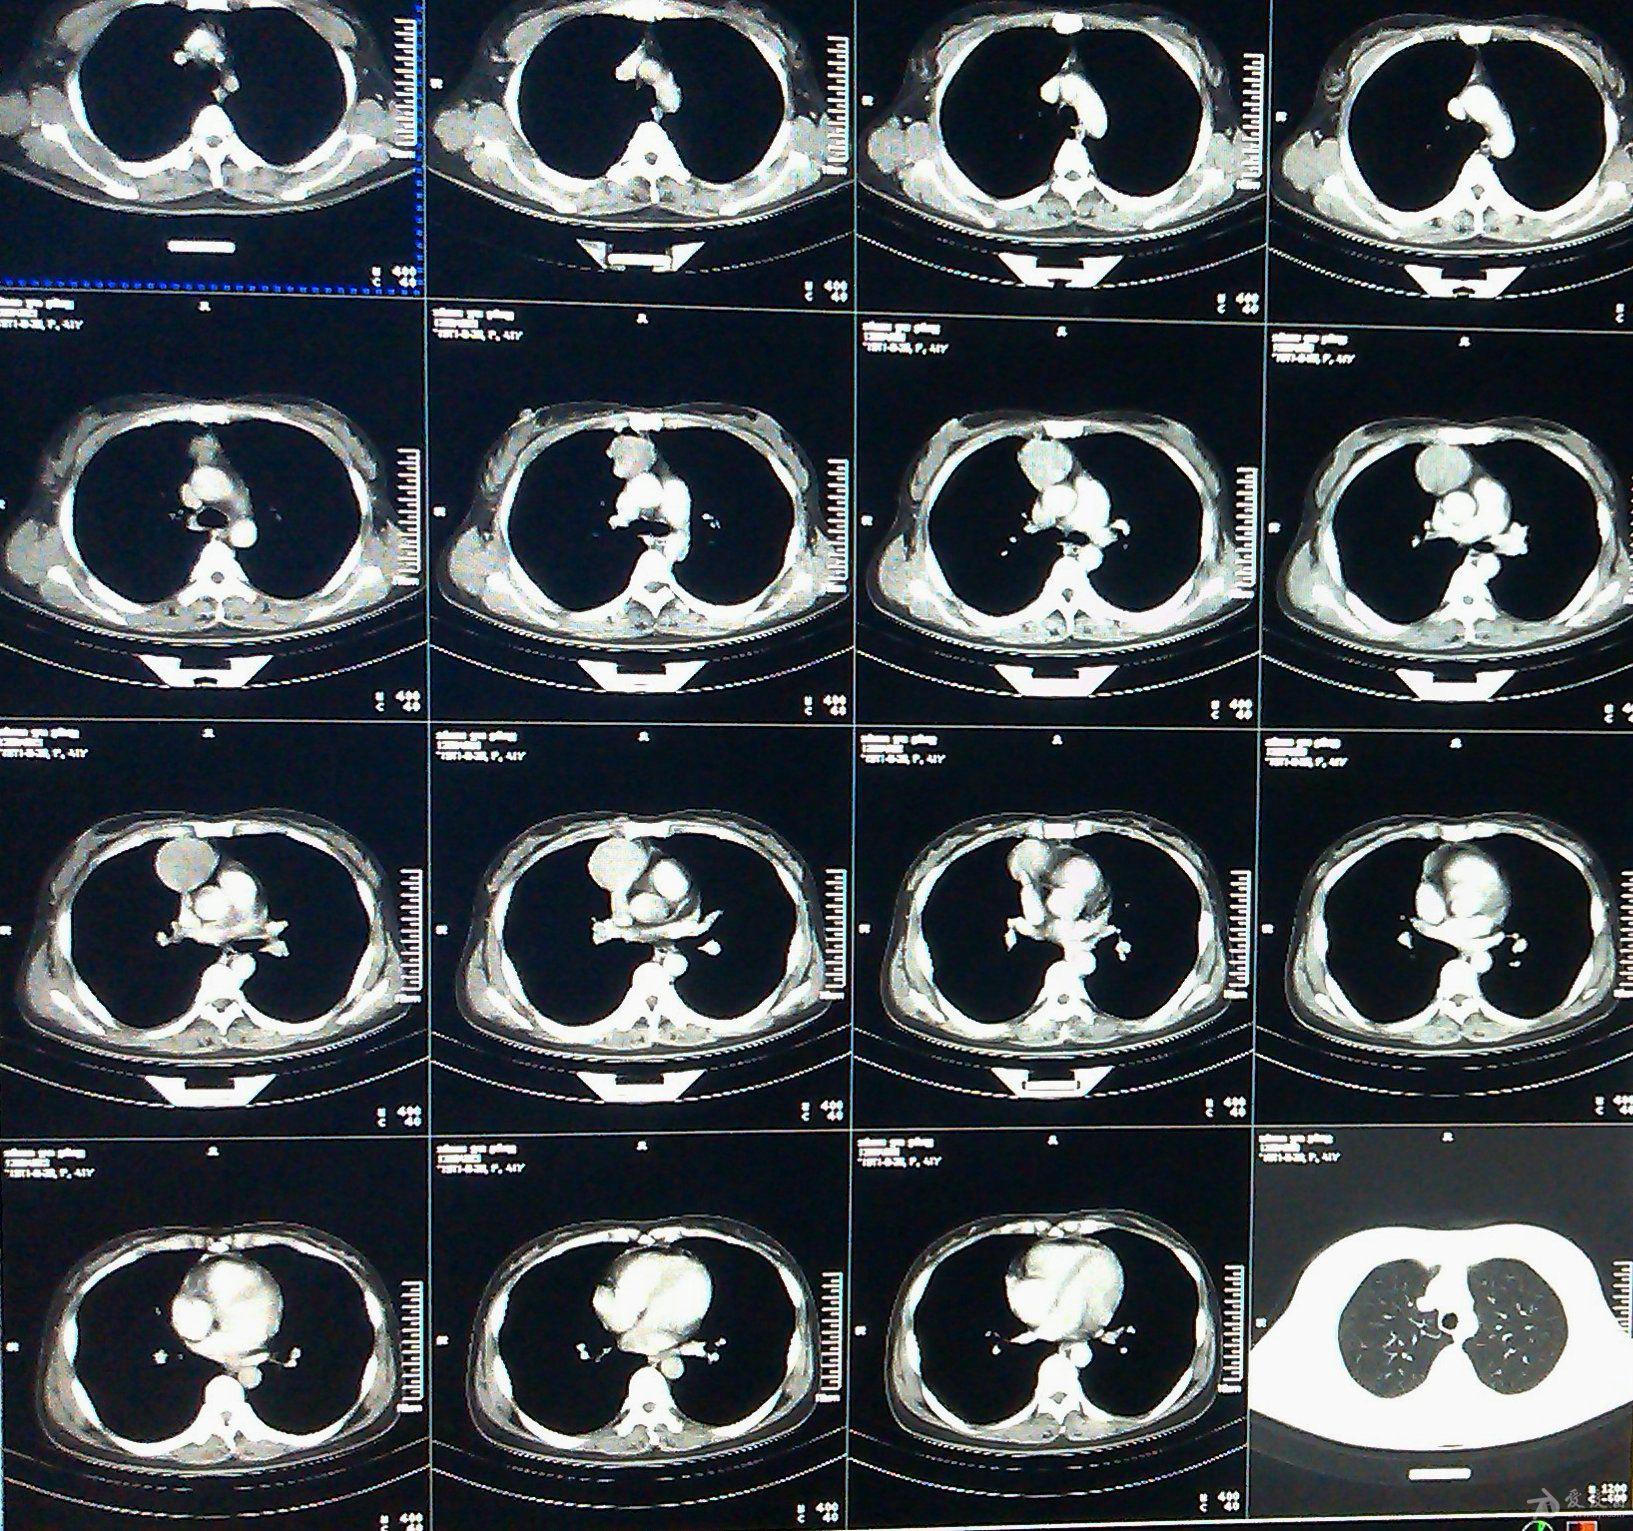

这是术前的ct片:提示左肺明显巨大高密度影!

女性,无任何自觉症状,体检肺ct平扫 增强

肺部ct影像是什么病.请教各位老师